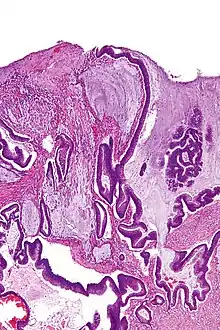

Micrograph of a mucinous adenocarcinoma of the colon. H&E stain.

A mucinous neoplasm (also called colloid neoplasm) is an abnormal and excessive growth of tissue (neoplasia) with associated mucin (a fluid that sometimes resembles thyroid colloid). It arises from epithelial cells that line certain internal organs and skin, and produce mucin (the main component of mucus). A malignant mucinous neoplasm is called a mucinous carcinoma. For example, for ovarian mucinous tumors, approximately 75% are benign, 10% are borderline and 15% are malignant.